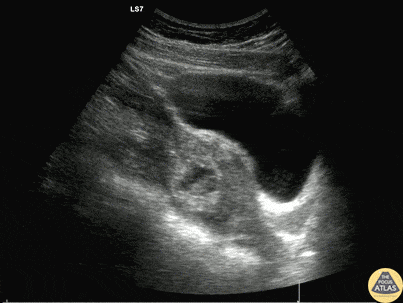

A 20s F presented with syncope in the setting of multiple days of abdominal pain which acutely worsened. She arrived hypotensive, tachycardic, and on FAST exam, had free fluid in the right and left upper quadrants as well as suprapubic window. Serum beta-hCG testing was positive. A detailed examination of the adnexa is shown here, demonstrating a ruptured ectopic pregnancy. This patient received blood via massive transfusion protocol and was taken emergently to the OR, where an exploratory laparotomy demonstrated an ectopic pregnancy and more than 2L of hemoperitoneum. Dr. Will Dewispelaere, PGY2, and Dr. Greg Wiener, PGY4 Denver Health Residency in Emergency Medicine